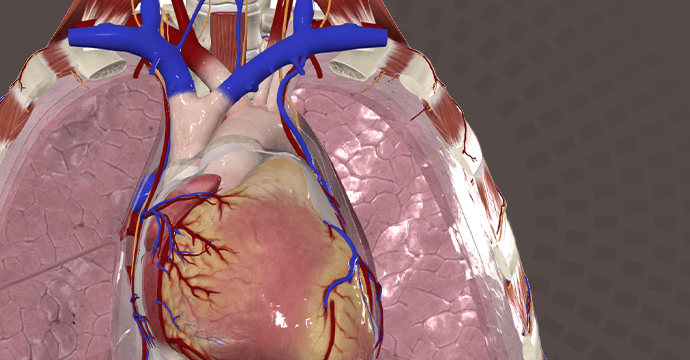

Take your understanding of human anatomy to the next level. Our comprehensive resources combine detailed information and stunning illustrations!

Enhance your studies for a truly dynamic learning experience. Explore interactive anatomy models from Complete Anatomy. Start mastering anatomy today with our free anatomy flashcards designed for quick review on the go.